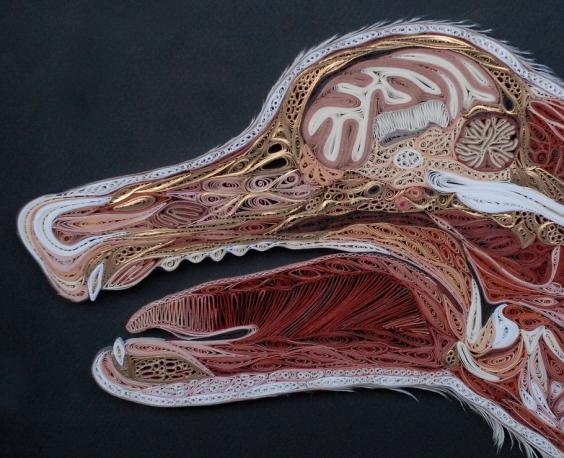

Nilsson'ın "Doku Serisi" adını verdiği çalışmasında insan ve hayvanlara ait beyin, kaslar, gövde ve birçok organın kesiti yer alıyor.